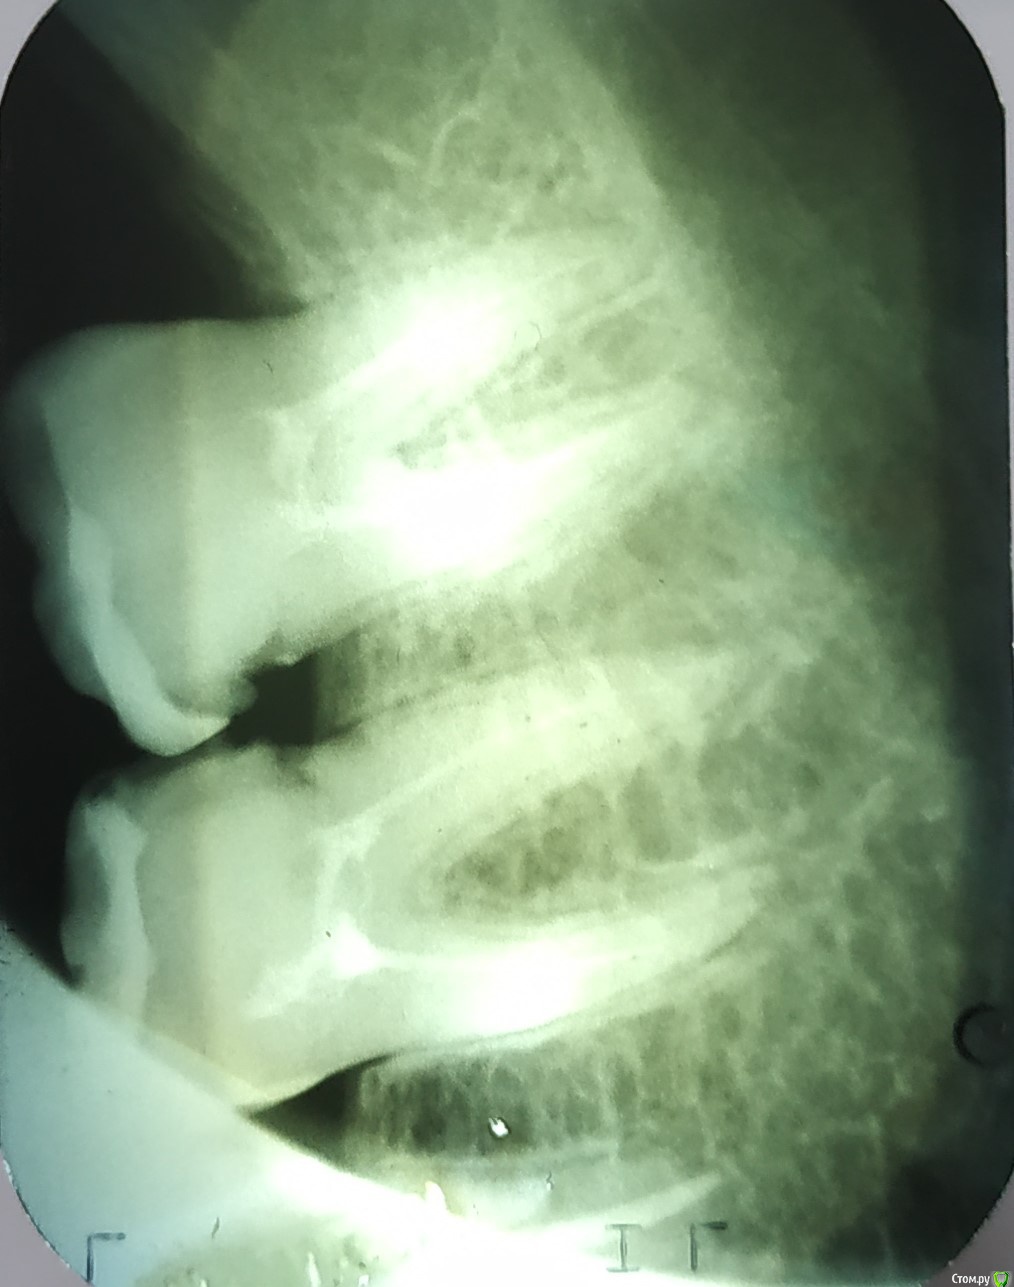

Vlad7772 Опубликовано 30 марта, 2019 Поделиться Опубликовано 30 марта, 2019 (изменено) Добрый день. Подскажите как быть. Прошлым летом (приблизительно 07.2018) обратился к доктору, болели зубы 47 и 48, удалили нервы и запломбировали. Спустя месяц-полтора(08-09.2018) при накусывании появлялась очень сильная боль, которая прошла спустя 4-5 дней. После этого проблем не было.Недавно в марте текущего года (03.2019), начал ныть зуб после приема еды почти любой. Боль постепенно нарастала и в течении 5-10 минут уходила, боль ноющая, терпимо, но не приятно.Пошел к доктору, выяснили что болит 48 зуб, реагирует на поступивания и воду, опять же постепенно и спустя 5 минут проходит, зуб внешне цел, ничего не воспалено и не опухло.Сделал рентген, доктор сказал, ничего плохого на снимке не видит, возможно это сезонное, такое бывает. Следить за развитием, если будет болеть сильнее приходить к нему. Сказал принимать соленные ванны ( пол стакана воды с солью размешать) три раза в день.Подскажите что это может быть и как с эти бороться) не люблю когда зубы не в порядке, да и запускать не хочется.Мог ли я его простудить, так как перед этим, возможно, немого перемерз. Но перемерзал и раньше и проблем с зубами не было.Во общем, дайте пожалуйста совет, заранее спасибо. Изменено 30 марта, 2019 пользователем Vlad7772 2 Ссылка на комментарий

dok1 Опубликовано 1 апреля, 2019 Поделиться Опубликовано 1 апреля, 2019 Показано перелечивание каналов. Занее каналы были запломбированы неполностью Ссылка на комментарий

suballex Опубликовано 3 апреля, 2019 Поделиться Опубликовано 3 апреля, 2019 КТПерелечиваниеПломбирование скрытых кариозных, тоже было бы не плохо.Коронки, либо вкладки Ссылка на комментарий